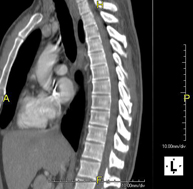

- Tórax- TC Tórax Prueba diagnóstica que consiste en obtener imágenes del tórax de alta definición anatómica (pulmones, corazón, mediastino, grandes vasos, caja torácica, etc.) mediante el empleo de un equipo de TC (Tomografía Computarizada). Dichas imágenes se estudian posteriormente en una estación de trabajo que permite reconstrucciones bidimendionales en diferentes planos del espacio y también reconstrucciones 3D (volumétricas). Algunos estudios requieren el empleo de contraste yodado para mejorar la definición de las imágenes. Prueba diagnóstica que consiste en obtener imágenes del tórax de alta definición anatómica (pulmones, corazón, mediastino, grandes vasos, caja torácica, etc.) mediante el empleo de un equipo de TC (Tomografía Computarizada). Dichas imágenes se estudian posteriormente en una estación de trabajo que permite reconstrucciones bidimendionales en diferentes planos del espacio y también reconstrucciones 3D (volumétricas). Algunos estudios requieren el empleo de contraste yodado para mejorar la definición de las imágenes.

- TC Tòrax Prova diagnòstica que consisteix en obtenir imatges del tòrax d'alta definició anatòmica (pulmons, cor, mediastí, grans vasos, caixa toràcica, etc.) mitjançant l'ús d'un equip de TC (Tomografia Computeritzada). Aquestes imatges s'estudien posteriorment en una estació de treball que permet reconstruccions bidimensionals en diferents plans de l'espai i també reconstruccions tridimensionals (3D: volumètriques). Alguns estudis requereixen l'ús de contrast iodat per millorar la definició de les imatges. Prova diagnòstica que consisteix en obtenir imatges del tòrax d'alta definició anatòmica (pulmons, cor, mediastí, grans vasos, caixa toràcica, etc.) mitjançant l'ús d'un equip de TC (Tomografia Computeritzada). Aquestes imatges s'estudien posteriorment en una estació de treball que permet reconstruccions bidimensionals en diferents plans de l'espai i també reconstruccions tridimensionals (3D: volumètriques). Alguns estudis requereixen l'ús de contrast iodat per millorar la definició de les imatges.